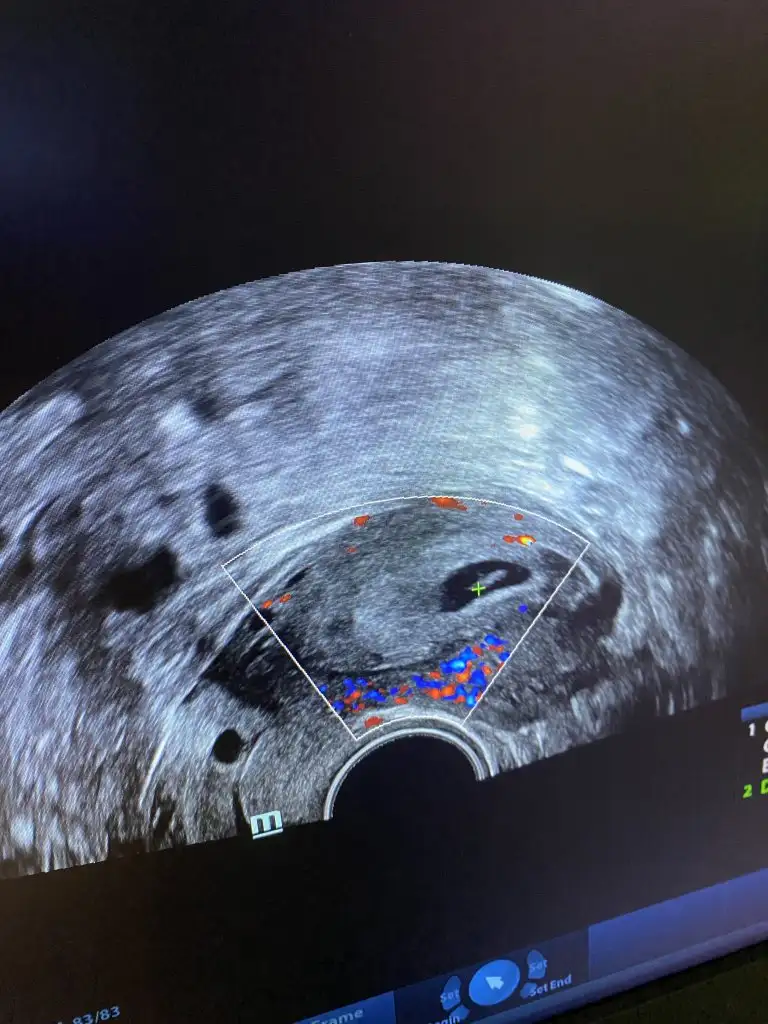

Evet gördük ama bu sefer kalbi atmadığını öğrendik doktor kürtaj yapmamız gerektiğini söyledi ama ben hala inanamıyorum 😔 ve beklemek istiyorum doppler ile baktı bebekte kan akımı yok cansız 😔

Özel doktora gidiyordum zaten takip ediyordu ilk hafta gittiğimde kalp atışları gayet iyiydi elhamdulillah bir hafta sonra gittiğimde iki tık tek duyduk kalbinin zayıf attığını söyledi 2 gün sonra tekrar gittiğimde ise hiç duyamadıpımı gördüm bide sigara çok içiyordum😔 acaba ondan dolayı kalbi durmuş olabilir mi 😔 zaten kan uyuşmazlığı da vardı eşimle